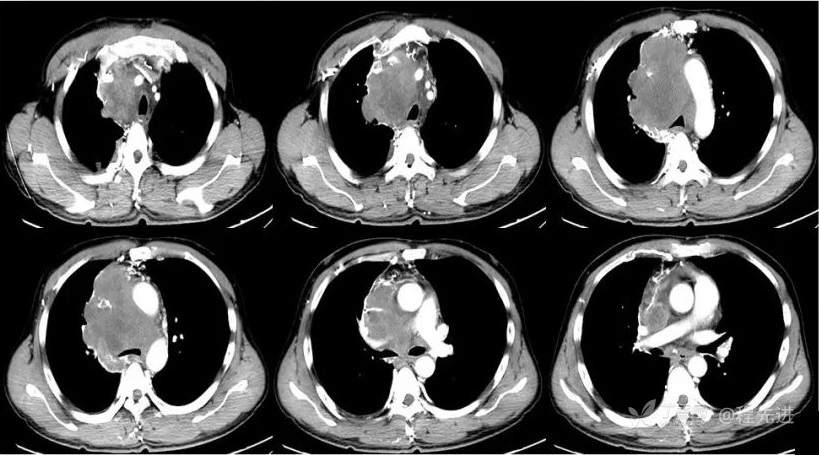

CT

平扫CT值约38HU,动脉期CT值约46HU,静脉期CT值约58HU